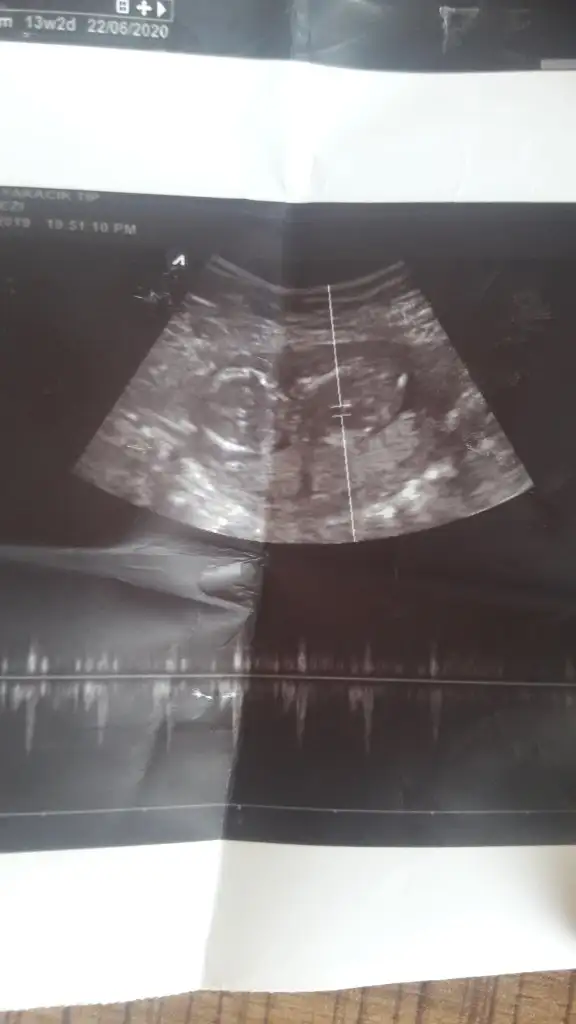

Kız gibi gibi sanki eminde değilim başka usg varmıArkadaşlar 13 haftalık yorumlarınızı bekliyorum çatladımmmmm

Biri 9+5 biri de 11+5. Yan donmus gibi belli oluyor mu bilemedimTekrar atsana foto

Kız gibiBiri 9+5 biri de 11+5. Yan donmus gibi belli oluyor mu bilemedim

Ikra erkek gibi dedi sen de kizKız gibi

Bende baştan erkek yaZdım sonra kız dedimIkra erkek gibi dedi sen de kizbakalim hangisi olacak cokkk tesekkurler